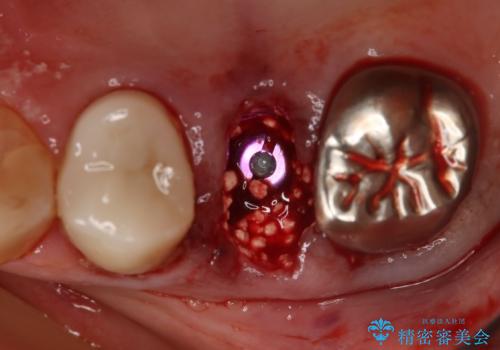

インプラント治療を希望されたので治療の期間・回数の少ない抜歯即時埋入インプラントでの治療を計画しました。

抜歯と同時にインプラントを埋入することで治療の期間・回数を減らし、患者様への負担を大幅に軽減することができます。

今回の患者様においては、術後に痛みは発生せず良好な経過を得ることが出来ました。